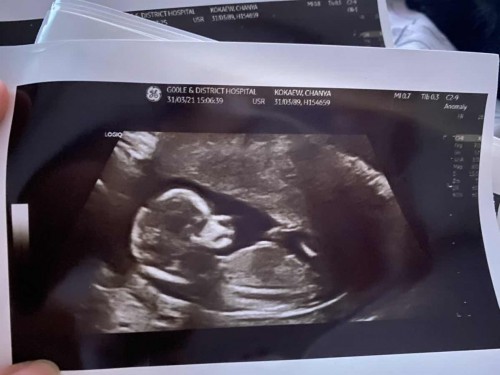

ภาพตอน 18W+6 D ตอนนี้ 22W+1D แล้วค่ะ #ท้อง2 👶#เด็กชายนะคับ